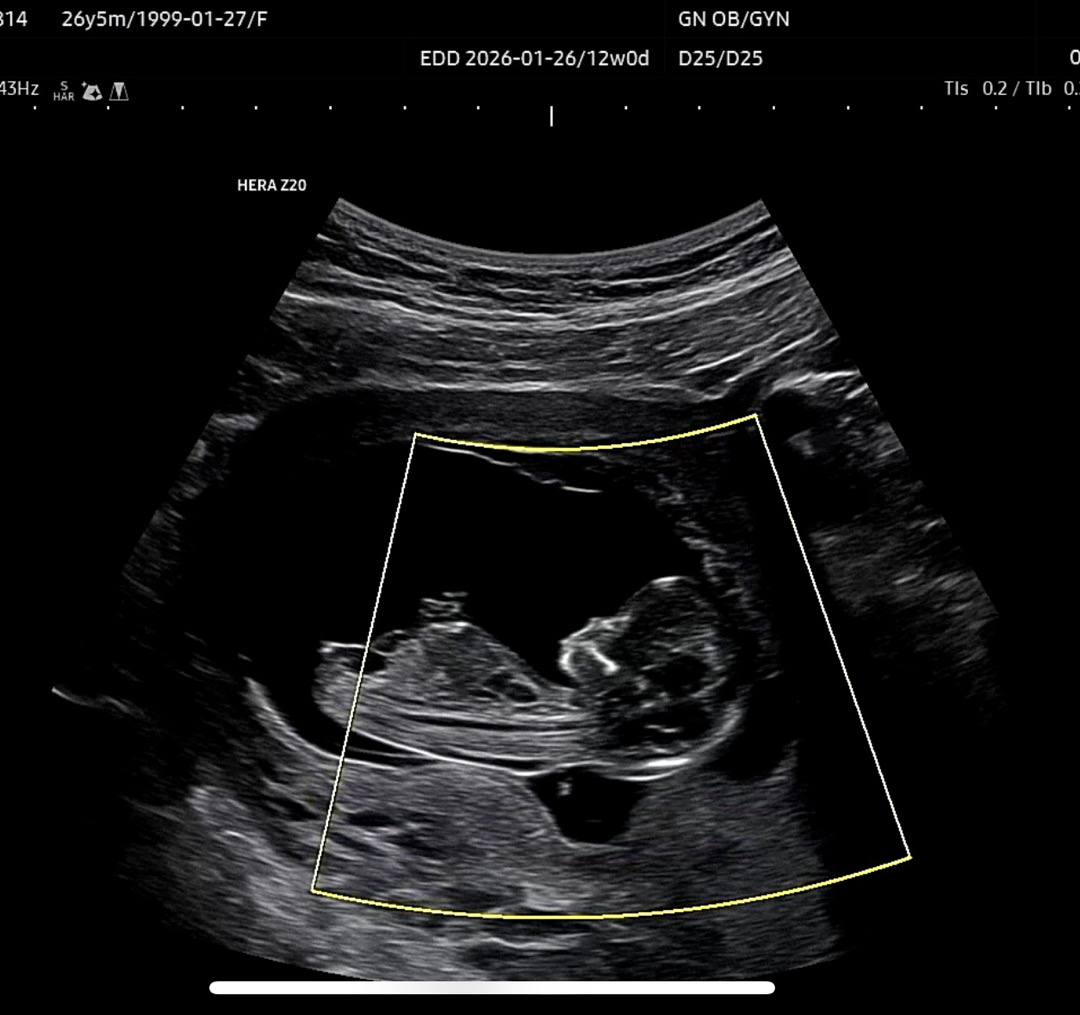

12주 입니다! 남편이랑 매일 눈 빠지게 보면서 긴긴가민가.... 하고있네요🥹😂 지나가시던 고수님들 의견 한번씩만 부탁드립니다!! 감사합니다🙏❤️